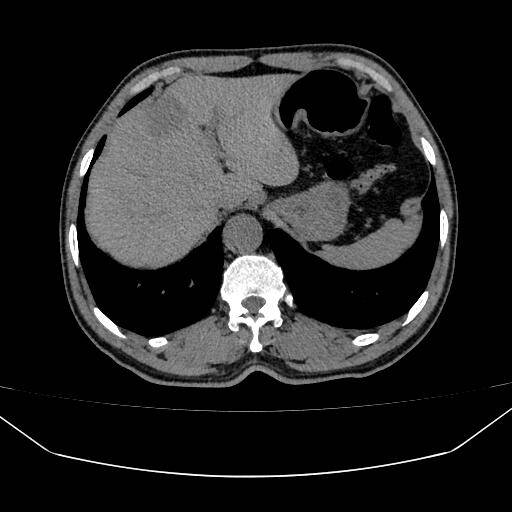

上腹部CT增强检查具备诸多显著优势。与普通CT相比,它通过注射造影剂,能让病变部位与正常组织形成更鲜明对比,哪怕是微小的病灶也难以遁形。在检查肝脏病变时,普通CT可能难以区分良性与恶性肿瘤,而增强CT则可以凭借病变部位的血液供应特点,精准鉴别肿瘤性质,为后续治疗方案的制定提供关键依据;在检测胰腺疾病时,它能清晰显示胰腺的细微结构和周围血管,有效提升早期胰腺癌的检出率,让患者获得早发现、早治疗的宝贵机会。

该检查在多种疾病的诊断中作用关键,能清晰显示肝脏、胆囊、胰腺、脾脏等器官的病变,对早期发现肿瘤、血管病变等意义重大。此前,社区居民若需此类检查,往往要前往大医院排队预约,既耗时又费力。此次影像科新服务的推出千汇网,极大地便利了社区居民,在家门口就能享受高质量的影像检查服务。